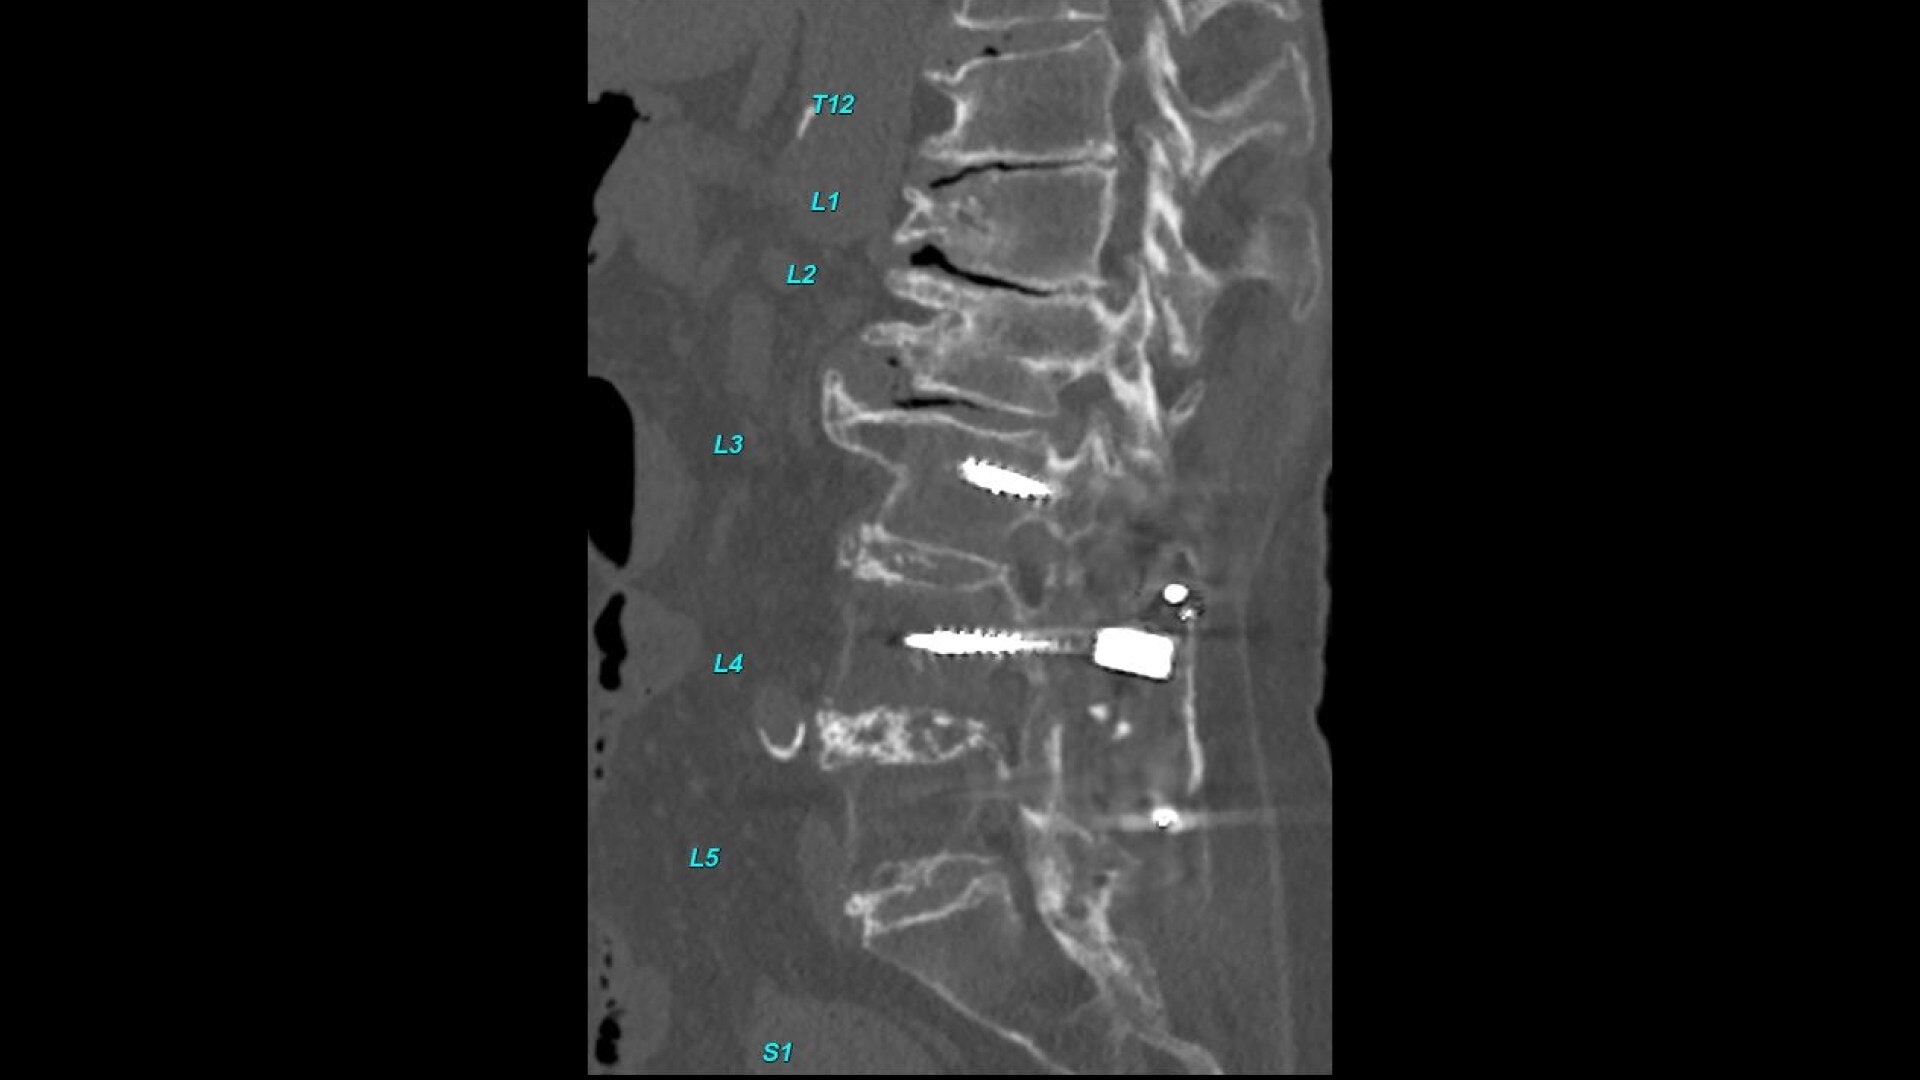

• Automated spine labeling

• Automated generation of a 3D trace to generate oblique and straightened reformat views

• Automated generation of oblique views perpendicular to vertebral bodies and disc spaces

• Easily edit the centerline to ensure accurate placement in the most challenging cases

• Accessible for any exam type: trauma, oncology, dedicated spine, general imaging